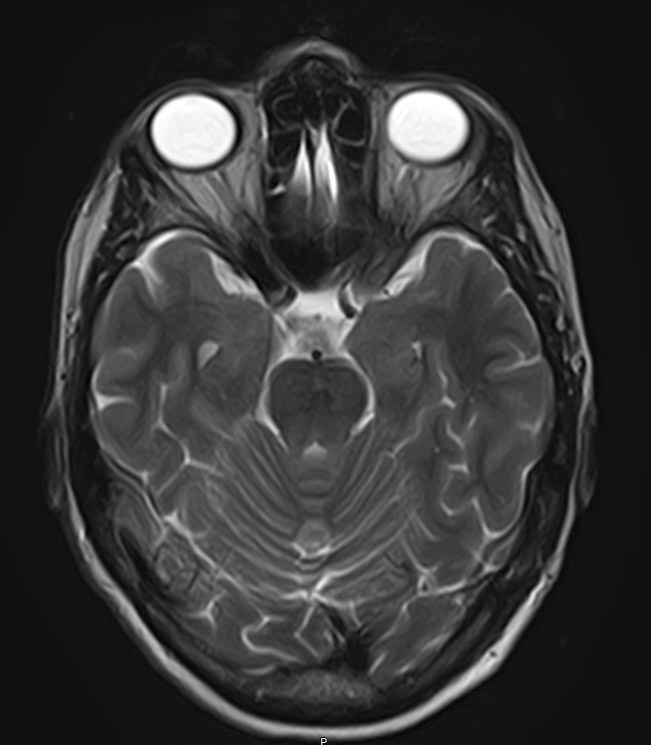

Для диагностики поражения черепно-мозговых нервов, а также оценки состояния окружающих их тканей и визуализации сосудистой сети головного мозга в клинике «Доступная медицина» проводится комплексное обследование МРТ головного мозга + Мр-ангиография головного мозга + МР-венография головного мозга + черепно-мозговые нервы. Данное обследование включает в себя несколько протоколов: стандартный – для оценки состояния всех структур головного мозга и дополнительные – для изучения очагов поражения черепных нервов и визуализации всей сосудистой системы головного мозга.

Исследования выполняются на современном высокопольном томографе экспертного класса TOSHIBA VANTAGE TITAN 1,5 Тесла, который использует разные режимы сканирования с толщиной среза от 1мм в различных плоскостях с последующей цифровой обработкой полученных данных для создания трехмерных изображений. МР-ангиография отображает состояние артериальной системы кровоснабжения головного мозга. МР-венография головного мозга позволяет детально изучить особенности венозного русла головного мозга.

Компьютерная программа обрабатывает данные, полученные при сканировании, и формирует объемные изображения как самого мозга, так и сосудистой системы в отдельности без прилегающих тканей. Методики применяются одновременно и взаимодополняют друг друга.

Данное комплексное исследование в большинстве случаев проводится с контрастным усилением, которое необходимо для улучшения визуализации черепно-мозговых нервов. Для этого внутривенно вводится препарат, содержащий гадодиамид (соли металла гадолиния) для получения изображений с высокой четкостью и контрастностью, что способствует ранней диагностике заболеваний головного мозга.